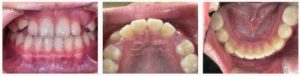

▼Before(治療前)

学校の歯科検診で「上の前歯が出ている」と指摘を受け、お母さまがご心配になり来院されました。

診察時、上の前歯が前方に突出しており、下唇が歯に引っかかるような状態で、

口を閉じるときに力を入れないと唇が閉じにくい様子でした。